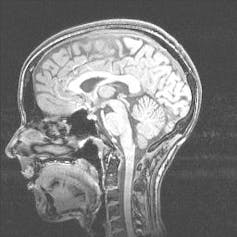

With the use of high resolution functional Magnetic Resonance Imaging (fMRI), scientists have been able to measure activity in the brains of people while they view coloured pictures and films. This resulted in a series of “snapshots” of a complex system at work. This technology has allowed us to develop a better understanding of how the brain responds to colour.

Neuroimaging has confirmed that some parts of the brain respond more strongly to colour than others. But generally, imaging has revealed that colour processing is more distributed) through the visual cortex than previously thought.

In a recent study, we measured the visual cortex response of subjects watching full colour and black-and-white clips from Baz Luhrmann’s Strictly Ballroom. We found that, in addition to a strong colour response in a hypothesised “colour area”, there was also a strong preference for colour in other areas, from which the “colour area” receives input. This finding adds to evidence against the notion that colour is a feature extracted by and represented in a restricted visual area within the brain.

Looking at a normally functioning human brain is of particular importance when we want to understand not just what functions different areas of the brain perform, but how different parts of the brain interact.

These insights help us understand how the brain processes information about colour. And further research in this area will hopefully help us understand brain processing more generally. Neuroimaging provides us with the ability to look inside a normally functioning human brain, rather than basing conclusions on specific cases of brain injury.